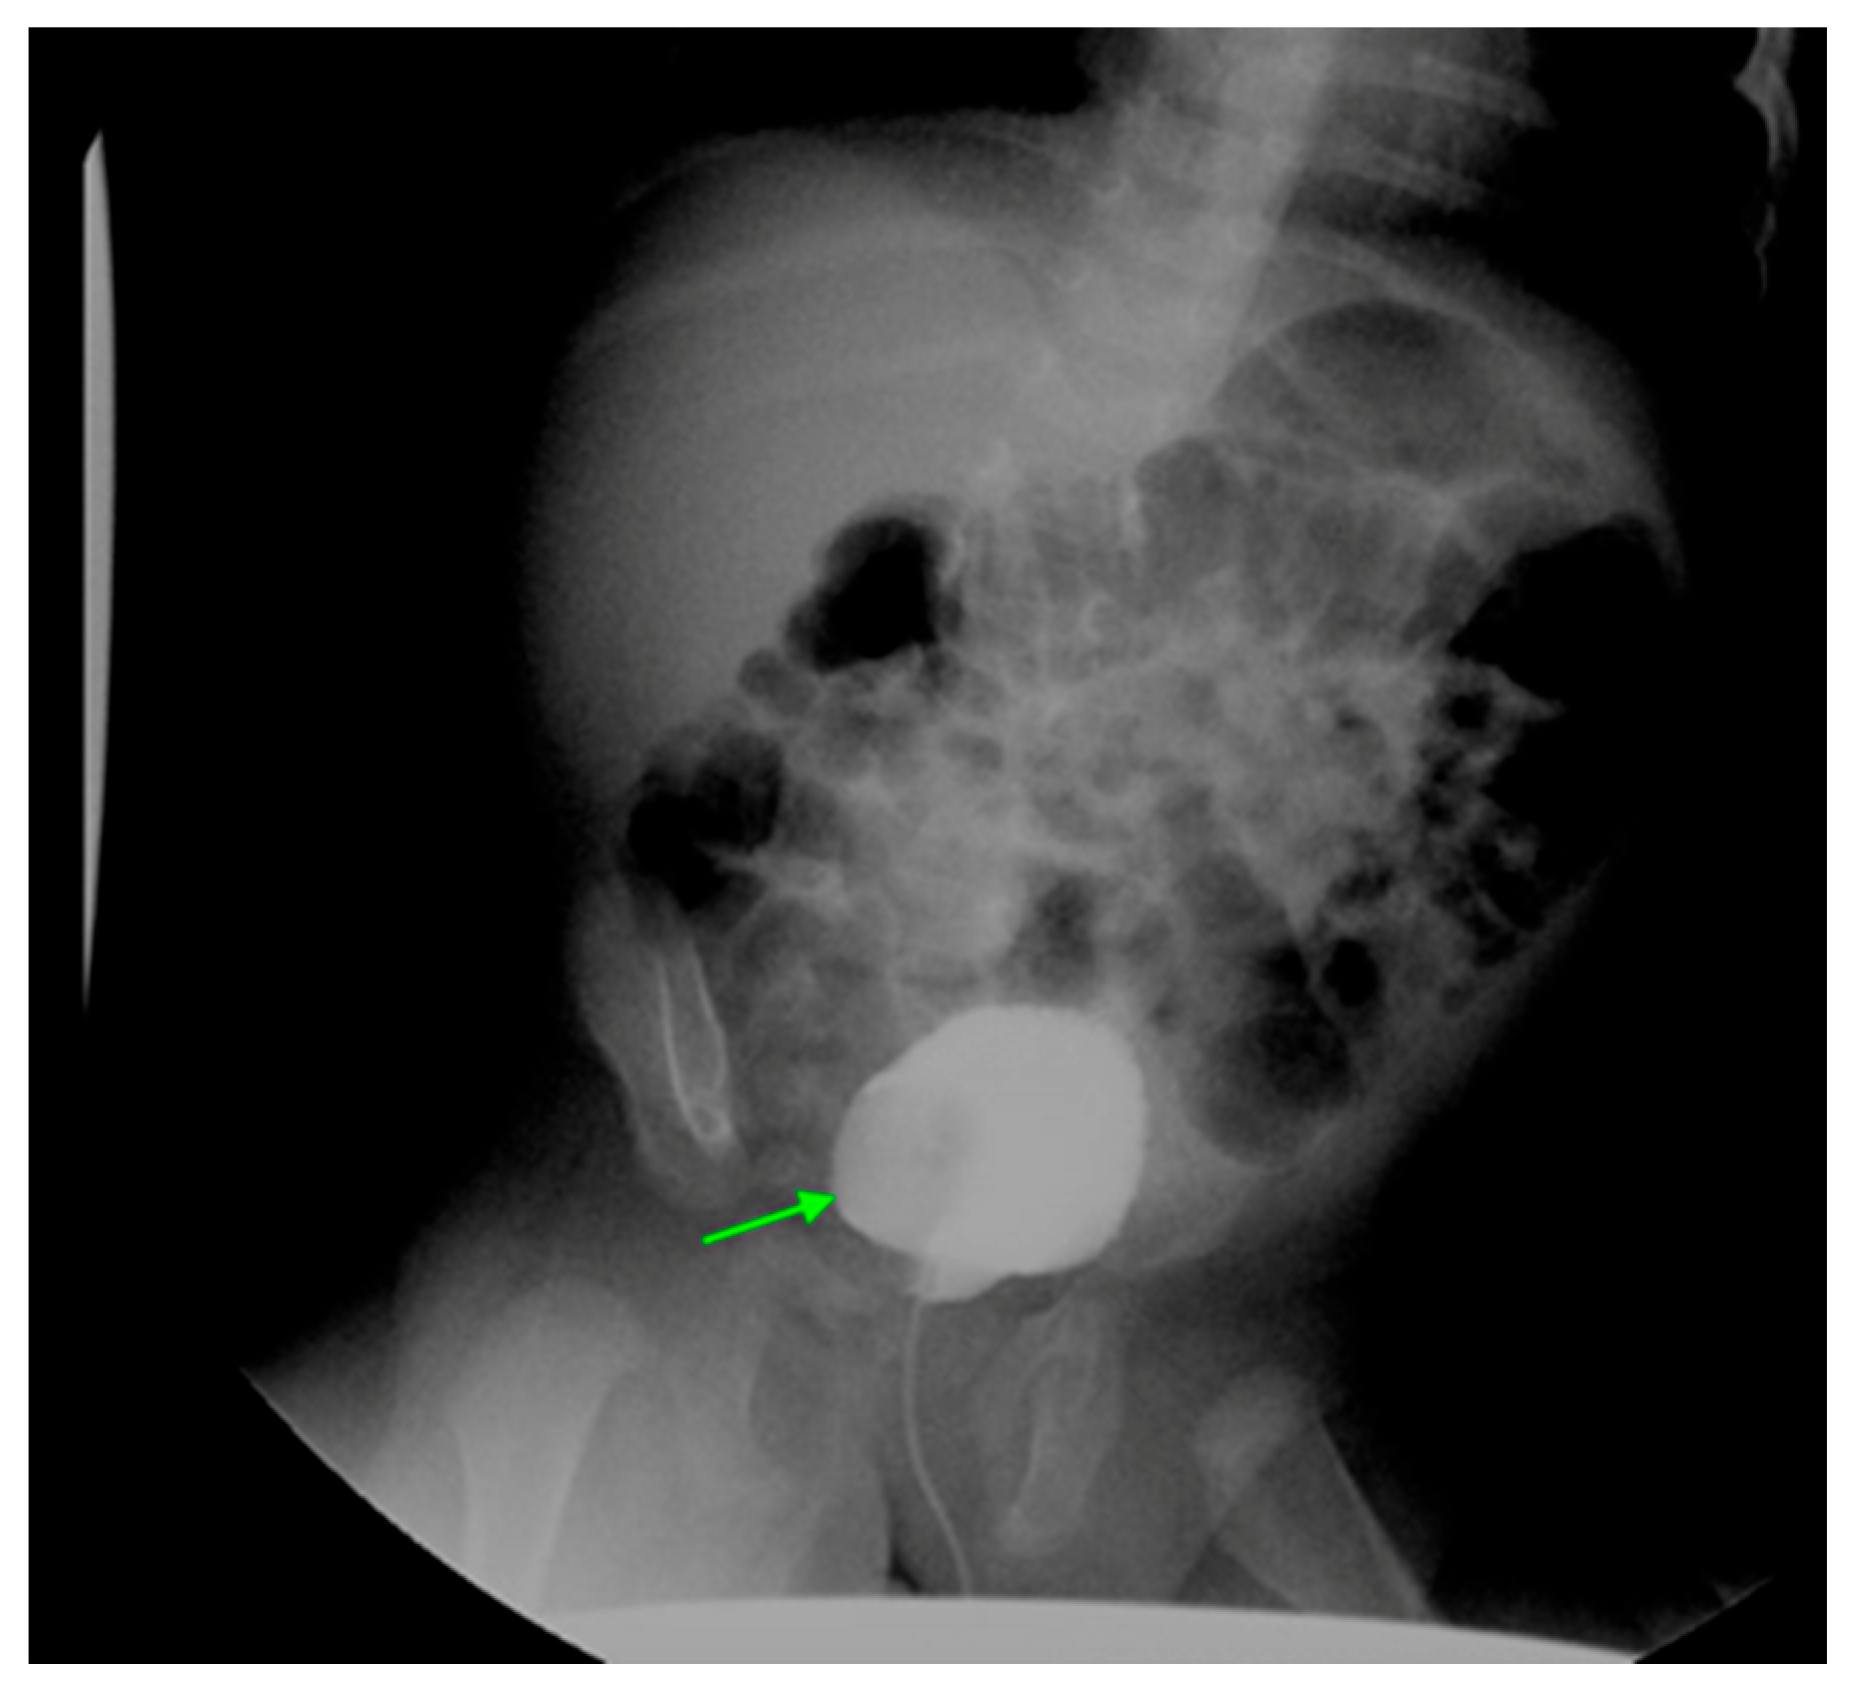

16. Vesicoureteral Reflux